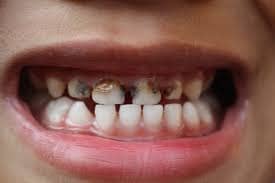

*Caries de infancia temprana en estado avanzado

Esta se caracteriza por provocar un proceso destructivo rápido de los dientes (incisivos superiores inicialmente), pues la capa de esmalte dental de los dientes de leche es mucho más delgada y débil que la de los dientes permanentes, además anatómicamente son mucho más pequeños por lo que la caries llega con mayor rapidez al nervio, aumentando así las posibilidades de formar un absceso dental.

La primera manifestación de la caries de infancia temprana es una mancha blanca en forma de media luna o semicírculo en la parte superior del diente cerca a la encía, pronto la mancha cambiará a un color amarillo claro o negro y comenzará a extenderse hacia los lados y hacia abajo como se muestra a continuación:

*Caries de infancia temprana en su etapa inicial, intermedia y en estado avanzado